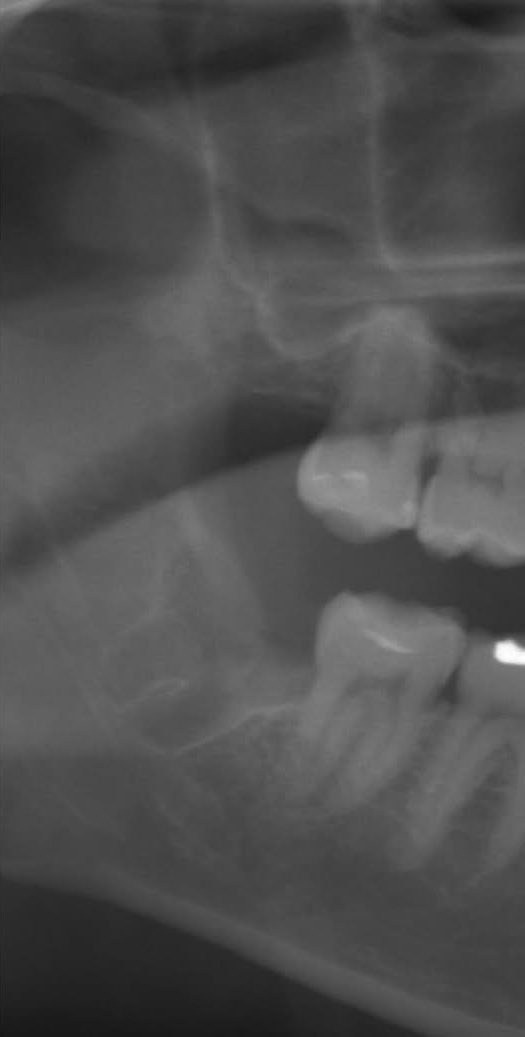

抜歯後

| 治療名 | 親知らず抜歯(難抜歯) |

| 治療内容・説明 | 歯根が開いており先端も太く、下歯槽神経に近接している親知らずの抜歯症例です。手前の歯に食い込んでおり、時々腫れを繰り返していただため抜歯をご希望されました。周囲の歯槽骨を削合してから歯を分割し、慎重に抜歯を行いました。親知らずは骨が硬くなる前の若いうちに抜歯した方が、術後の負担が軽減されます。欧米では将来のトラブルを予防するための早期親知らず抜歯を「ウィズダムトゥースアウト(Wisdom Tooth Out)」と呼び、一般的に行われています。 |

親知らずの抜歯は、歯の位置や形態、神経との位置関係により難易度が大きく異なります。当院ではCT撮影により事前に詳細な診断を行い、安全な抜歯を心がけています。